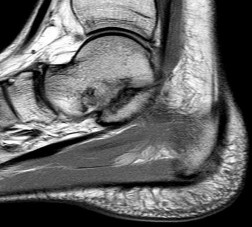

Figures 1a through 1c

Tarsal coalitions occur when primitive mesenchymal cells fail to differentiate and form the

normal articular separations between the tarsal bones of the hindfoot. Overall incidence is difficult to determine because many affected people are minimally symptomatic or asymptomatic. Symptomatic tarsal coalitions typically present in adolescents as a painful flatfoot; however, there are a number of possible presentations, and occasionally symptoms do not appear until adulthood. Most tarsal coalitions are between the calcaneus and the navicular (CN) and the talus and the calcaneus (TC). Although most TC coalitions are across the middle facet, posterior facet coalitions do occur. Plain radiographic evaluation of suspected tarsal coalition is the mainstay for diagnosis. However, coalitions can be bony or fibrous, and making the diagnosis can be difficult. The addition of CT images to distinguish bony definition and MR images to decipher soft tissue can aid in diagnostics. Bony coalitions appear as definite bony bridging between the bones, while fibrous coalitions are suspected when distortion of the bony anatomy is seen. Bony coalitions are best seen on the oblique view (CN) and Harris axial view (TC). There are a number of secondary signs such as the anteater (AE) sign (elongation of the anterior process of the calcaneus as it extends to the navicular as seen on the lateral view [CN]). talar beaking (traction spur of the talar neck thought to result from abnormal stresses as seen on the lateral view [both CN and TN]), and the “C” sign (a continuous cortical contour from the medial talus to the sustentaculum tali [ST]) as seen on the lateral view (TC). A number of newer signs are not as well known, such as a broad mediolateral dimension of the navicular on the anteroposterior (AP) view (the

navicular is wider than the talar head [CN]), nonvisualization of the middle facet on the lateral view (TC), the brick sign (a normal ST is flat, but a distorted ST is enlarged and curved [CN]), and a tapered lateral navicular bone as seen on the AP view (the medial navicular [CN] is much thicker than the lateral navicular).

Figure 1a shows talar beaking (TB), an AE, and an open middle facet (MF). Figure 1b shows a wide navicular (WN), and Figure 1c shows an abnormal articulation between the calcaneus and the navicular, all consistent with a CN coalition.